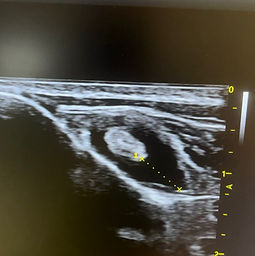

Bilde viser en kraftig bicepssene betennelse med økt væskeansamling rundt senen.

Senebetennelser. For eksempel biceps-sene betennelse, er en vanlig årsak til halthet hos aktive hunder. Det er ofte en halthet som kommer og går, og aldri blir helt bra. Med MSK Ultralyd kan vi da monitorere responsen på tilhelingen av skaden, for å tilrettelegge riktig aktivitet og behandling. Slik at det blir minst mulig risiko for tilbakefall av skaden når hunden settes igang igjen.